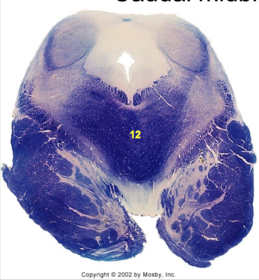

| Spinal tract of V | |

| Spinal nucleus of V | |

| Medial vestibular nucleus | |

| Inferior vestibular nucleus | |

| Dorsal cochlear nucleus | |

| Ventral cochlear nucleus | |

| Inferior olivary complex | |

| Inferior cerebellar peduncle | |

| CN IX | |

| Anterior spinocerebellar tract | |

| Central tegmental tract | |

| Olivary internal arcuate fibers | |

| Solitary tract | |

| Abducens root fibers | |

| Longitudinal pontine fibers (corticospinal tract) | |

| Transverse pontine fibers (dark fibers) | |

| Pontine nuclei (pale) | |

| Medial lemniscus | |

| ALS | |

| Trapezoid body | |

| Ventral trigeminothalamic tract | |

| Superior olive | |